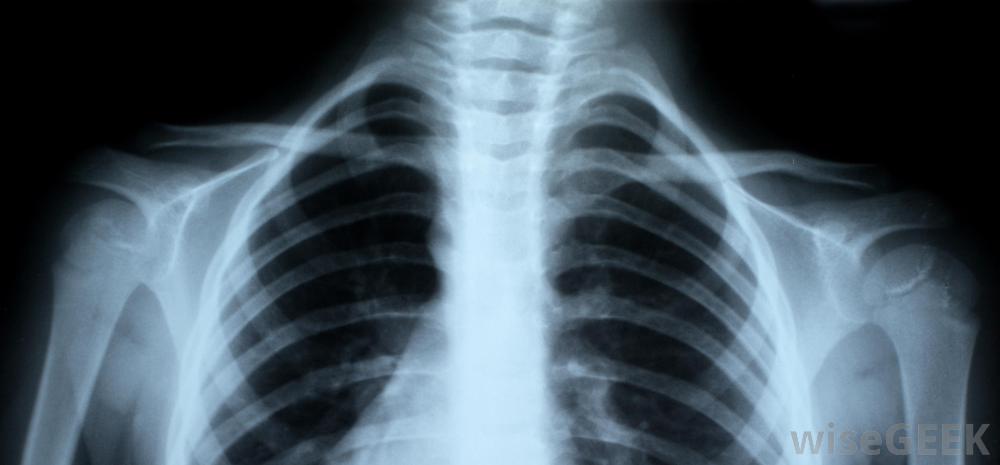

射线照片可以向医生显示锁骨是否断裂锁骨骨折愈合的时间长短取决于患者的年龄儿童通常在三到四周后痊愈。青少年可能在六到八周后痊愈,但是一个成年人可能要等四个月。一条吊带或八字形绷带可能要一直戴着。许多医生更喜欢吊带而不是绷带,因为一个人戴着八字形绷带时不可能正确地清洗,而且绷带会比绷带更不舒服,会引起更多的皮肤刺激。对于锁骨骨折的病人,可能会开出或推荐不同形式的止痛药,冷敷20分钟左右建议每两小时进行一次,以帮助减轻疼痛和减轻肿胀。疼痛消退后,最好开始移动手臂、手腕和肩膀,以防止其僵硬。医生或理疗师可以教患者进行可以保持手臂的锻炼活动。在断开的锁骨完全愈合之前,不应尝试运动和其他力量锻炼。有时手术是治疗锁骨骨折的最佳选择。这通常发生在开放性骨折或者如果骨头没有愈合。在手术过程中,医生可能需要植入钢板或螺丝钉。手术也可能是清理伤口和防止感染的必要手段。然而,锁骨骨折的手术并不常见,而且骨头通常在没有任何干预的情况下愈合